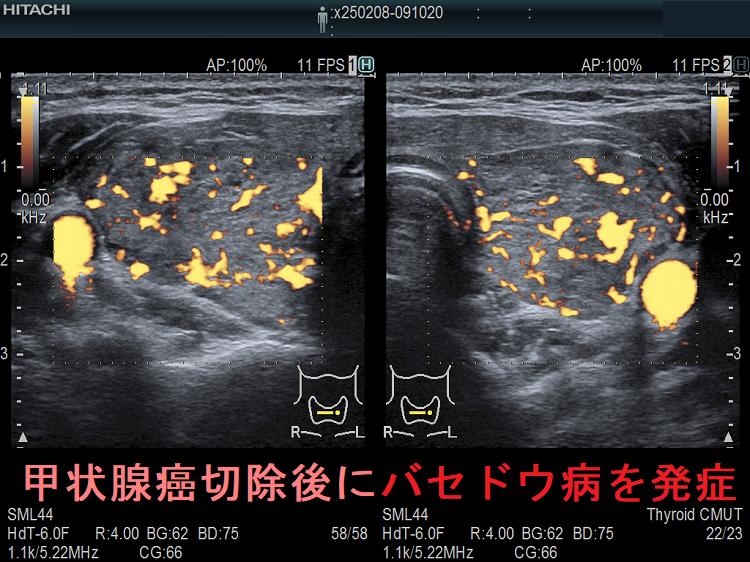

長崎甲状腺クリニック(大阪)で採用している抗甲状腺薬の中止基準(抗甲状腺薬の中止基準)・アイソトープ(放射性ヨウ素)治療・手術療法での再発はありません(ただし、中途半端な甲状腺亜全摘術を除く)。

一般的な抗甲状腺薬の中止基準を用いてバセドウ病治療を中止後、再度甲状腺ホルモンが上昇して来たら、78%はバセドウ病の再発ですが、22%は一時的な甲状腺の破壊による無痛性甲状腺炎です(「上條甲状腺クリニックの甲状腺疾患Q&A」より)。

上條甲状腺クリニックの統計によると、バセドウ病/甲状腺機能亢進症の再発は、

- 1年以内再発62%

- 2年以内再発85%

- 3年以内再発92%

で、結局ほとんどが再発し、よくこんな中止基準を作ったものだと思います。